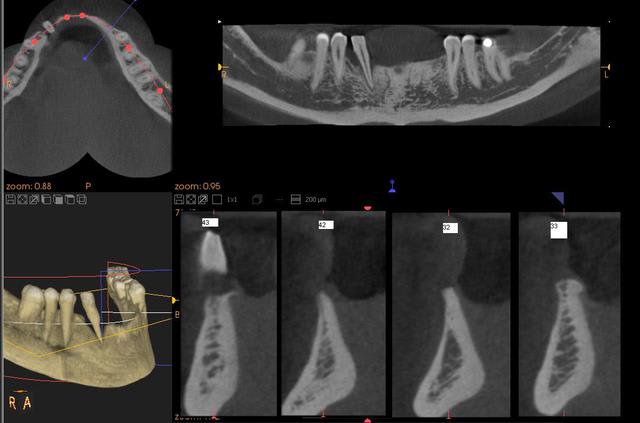

le plan de traitement consiste a poser 4 implants 43 42 33 32 et un bridge de 6 éléments.

Quelle épaisseur as tu au niveau des 3?. Si c'est suffisant, que penses tu d'implanter uniquement en 33 et 43?. Incisives et canines ont l'air de se placer quasi sur une ligne droite sur ton Wax up...

henri, il y a 3 mm au niveau des canines, et un bridge de 6 éléments sur 2 implants, je trouve cela un peu chaud.

Je pense que je vais faire faire une maquette 3D de la mandibule d'apres scanner d'ici un mois ( je laisse cicatriser au niveau de 42 ), pour poursuivre ma reflexion, et eventuellement préparer les blocs a l'avance, si bloc.

Pour le fichier STL, il est issu du cône beam d'étude , la 42 à été extraite depuis. Il faudrait peut-être refaire un autre cône beam, ou un scan si travaille avec posit, il n'aime pas le kodak 9000 !

Marc pour avoir eu les fichiers dicom et le modèle "en vrai" dans les mains, c'est très très fin et très très dense